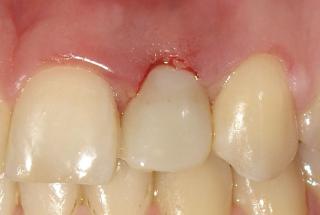

Clinical cases

MPI closely monitors clinical cases in the market to ensure their correct functioning and successful outcome.